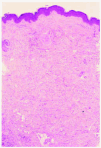

Se practicó una biopsia cutánea de una de las lesiones del paciente (fig. 5).

Fig. 5.--Colágeno maduro y compactado en dermis sin alteraciones inflamatorias. (Hematoxilina-eosina, x40.)

En el examen histopatológico se observa una epidermis normal, con una acumulación en la dermis de colágeno maduro y compactado, con ausencia de cambios inflamatorios, lo cual es compatible con nevos del tejido conjuntivo.